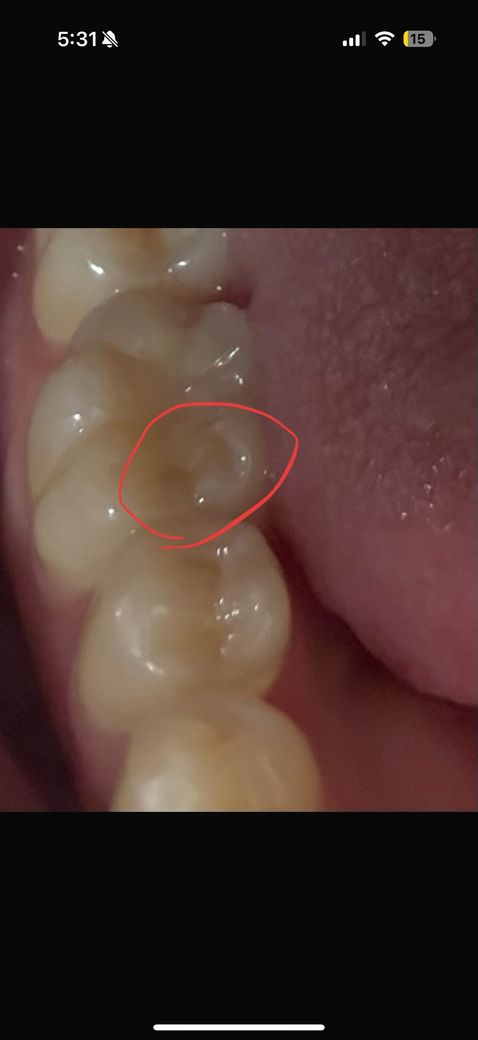

오늘갑자기 물마시는데 시려서 자세히봤는데 뭔가 깨진건지 패여보여서요 패인게맞나요?? 일시적시림이 아니고 치료가 필요할까요? 음식을먹거나 할땐 몰랐거든요 이쪽 윗니 임플란트해서 이쪽으로 거의안씹었었다가 오늘 이쪽으로 과자를 먹었어요.. 물마시니 시리네요 갑자기

일단 치아가 깨진부위가 잇어서 시릴수도 잇고 치경부 마모증때문에 시릴수도 잇으니 일단 치과에 가셔서 검진을 받아보세요.

치료가 필요한 정도의 마모나 충치가 보이진 않습니다만 증상이 지속된다면 엑스레이 찍고 안쪽 충치가 있는지 확인해봐야 합니다

사진으로는 정확한 확인이 어려워 보입니다 치아가 깨지거나 치과 충전물이 탈락했다면 치료가 필요할수도 있습니다.

자세한 확인을 위해서 치과에서 진료를 받아보는 것을 권유드립니다.